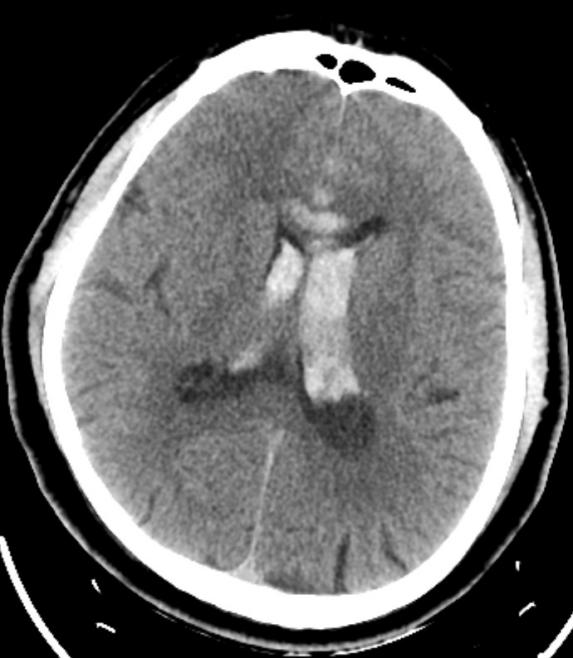

手术于复合手术室进行。先用血管造影机行CT检查提示脑室出血增多,脑室铸型,急性脑积水形成。团队立即行左侧脑室钻孔引流术,于左侧脑室内放置脑室引流管,颅内压极高,引流血性脑脊液。随后行脑血管造影提示左侧大脑前动脉A2段动脉瘤,团队采取微创治疗,应用支架辅助,于动脉瘤内填入3枚弹簧圈,造影显示动脉瘤完全闭塞,载瘤动脉通畅。手术历时3小时,手术完毕后行CT检查未见新发颅内出血,脑室引流管位置良好。

▲栓塞前